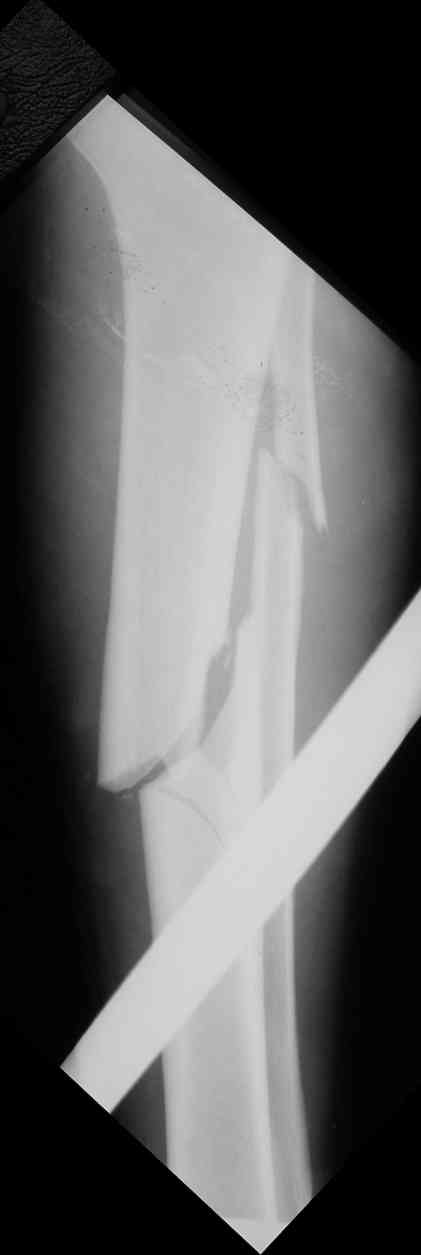

Вчера первый раз синтезировали голень гвоздем Fixion.

Спиральный оскольчатый перелом, ниже середины, у молодого парня. Сделали "классический" вариант гвоздя, который еще без винтов. Получилось все легко. Не торопясь, сделали операцию минут за 20. См. фото.

В отношении ранней нагрузки при спиральных переломах лучше не торопиться. По данному случаю необходимо достигнуть исчезновения щели между штифтом и внутреним кортексом по Rg. А так картинка прекрасная - и длина сегмента и репозиция. Можно поздравить, коллега!